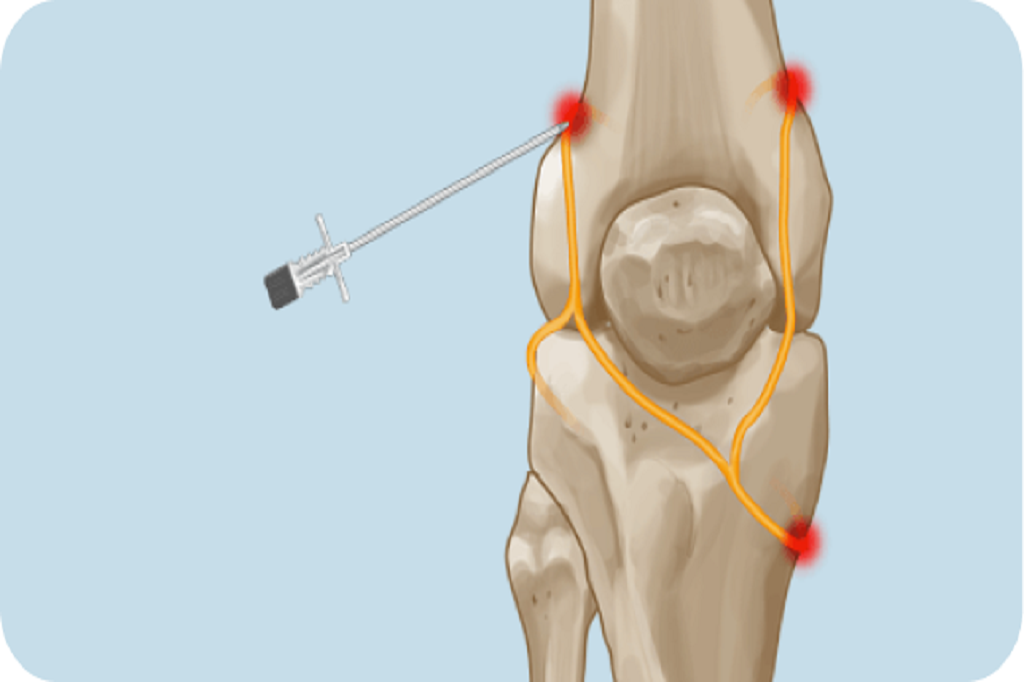

Corticosteroid injections for potent short-term relief or Platelet-Rich Plasma (PRP) to promote long-term healing.

A two-step process. First, a diagnostic nerve block identifies the pain source.If successful, Radiofrequency Ablation is used to provide long-lasting relief.